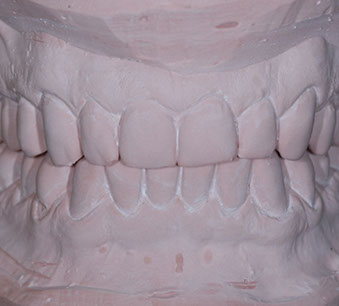

due impronte della bocca da cui si ricaveranno dei modelli in gesso